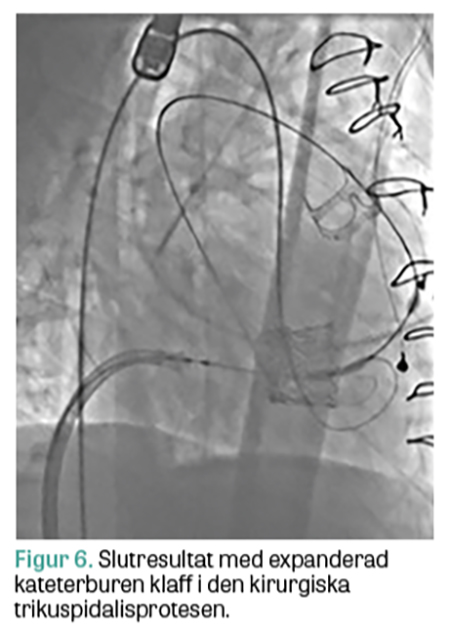

Hos några patienter har man dock noterat en relativt snabb degeneration av inopererade kirurgiska bioproteser, vilket leder till förnyade symtom av hjärtsvikt. Orsaken är troligen en fortsatt hög tumörinducerad hormonaktivitet, trots farmakologisk behandling, som även påverkar klaffproteserna. Dessa patienter kan då kräva ett andra ingrepp där risken med förnyad öppen hjärtkirurgi kan vara alltför stor för att vara rimlig. Kateterburen klaffintervention (transcathether aortic valve implantation, TAVI) är i dag rutinförfarande vid behandling av uttalad aortastenos, men görs även relativt enkelt på patienter med degenererade biologiska aortaklaffproteser (»klaff i klaff«), framför allt kirurgiska, men framgent kan det också förväntas behövas i degenererade TAVI-proteser. Vidare kan kateterburen klaffinplantation göras med gott utfall i degenererade mitralisproteser och i vissa fall även i mitralisringar, men där med sämre resultat [18]. På högersidan ökar erfarenheten av kateterburen klaffimplantation i trikuspidalisproteser och trikuspidalisringar [19], liksom i pulmonalisposition [20, 21]. Det ligger i metodens utveckling att också börja behandla karcinoidpatienterna med degenererade trikuspidalis- och pulmonalisproteser kateterburet, under förutsättning att grundsjukdomen är tillräckligt välkontrollerad. Akademiska sjukhuset i Uppsala bedriver en omfattande verksamhet vad gäller kateterburna klaffinterventioner framför allt mot aortaklaffen, men har en växande erfarenhet av ingrepp mot vitier i andra klaffpositioner. Vi har behandlat ett par patienter med karcinoid hjärtsjukdom med degenererade högerklaffar med kateterburen »klaff i klaff«-implantation (Figur 5 och 6). Med förbättrad onkologisk behandling kan man förvänta sig att gruppen av patienter med karcinoid hjärtsjukdom och degenererade bioproteser kommer att öka. I framtiden skulle patienter med karcinoid hjärtsjukdom som bedöms vara för sköra för traditionell öppen kirurgi teoretiskt kunna erbjudas en primär kateterburen åtgärd, både i trikuspidalis- och i pulmonalisposition.

Figur 6.